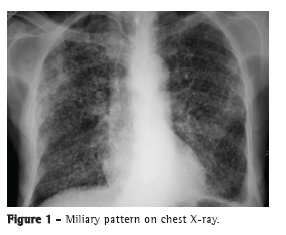

The most common radiological findings are reticular infiltrates and consolidation,(5,6,10,15,17) and cavitation can occur in 27-50% of cases.(6,10,16) Figures 1 to 4 show some of the main radiological patterns in this context.

The time from onset of symptoms to initiation of antituberculosis treatment has been reported to be over 30 days in 28.8-34.0% of cases.(6,17) The time from admission to initiation of appropriate treatment was evaluated in only one study, which reported a mean of 4.3 days. In that retrospective study, the time from admission to initiation of treatment was shorter in patients with miliary tuberculosis than in those with tuberculous pneumonia (2.8 ± 2.5 days vs. 5.0 ± 7.0 days; p = 0.048).(16) There can be a delay in diagnosis and, consequently, in initiation of treatment because it is difficult to differentiate tuberculous pneumonia from severe bacterial pneumonia on X-rays. Considering this difficulty in distinguishing the two pathologies, one study evaluated the differences between ICU patients with severe pneumonia and tuberculosis and those with severe pneumonia without tuberculosis in terms of their clinical and radiological characteristics. Symptom duration longer than two weeks and the presence of micronodules or a cavitary pattern on chest X-ray were significantly associated with active pulmonary tuberculosis.(20) In addition, a miliary pattern on chest X-ray can also be misinterpreted as congestive heart failure.(18)

In view of the aforementioned facts, the role of chest X-ray in the clinical diagnosis of pulmonary tuberculosis in ICU patients remains uncertain, and it is possible that chest X-ray does not contribute as much as expected. In a case-control study evaluating 89 patients with pulmonary tuberculosis and 89 controls, the most common radiological pattern was consolidation, which was found in 61 patients (6.5%). In the multivariate analysis, a history of pulmonary tuberculosis was associated with clinical suspicion of tuberculosis, although the radiological patterns were not associated with that suspicion.(21)